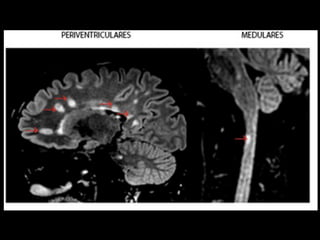

critérios  McDonald  (2017)   • disseminação  no  espaço   – RM  por  ≥  1  lesões  hiperintensas  em  T2,   sintomá+cas  ou  assintomá+cas,  que  são   caracterís+cos  de  EM,  em  dois  ou  mais  das   seguintes  quatro  áreas  do  sistema  nervoso   central:     • periventricular,     • cor+cal/justacor+cal,  infratentorial  e  medula  espinhal.

• Embora amplamentedifundidas, certas áreas são mais afetadas (>  sintomas) – Região periventriculares – Justacorticais – infratentoriais – Pedúnculos cerebelares – Tronco encefálico – Localização posterior ou lateral na Medula espinhal • As lesões tendem a ser simétricas e têm uma distribuição perivenosa (em torno de pequenas veias e vênulas), contendo linfócitos e macrófagos.